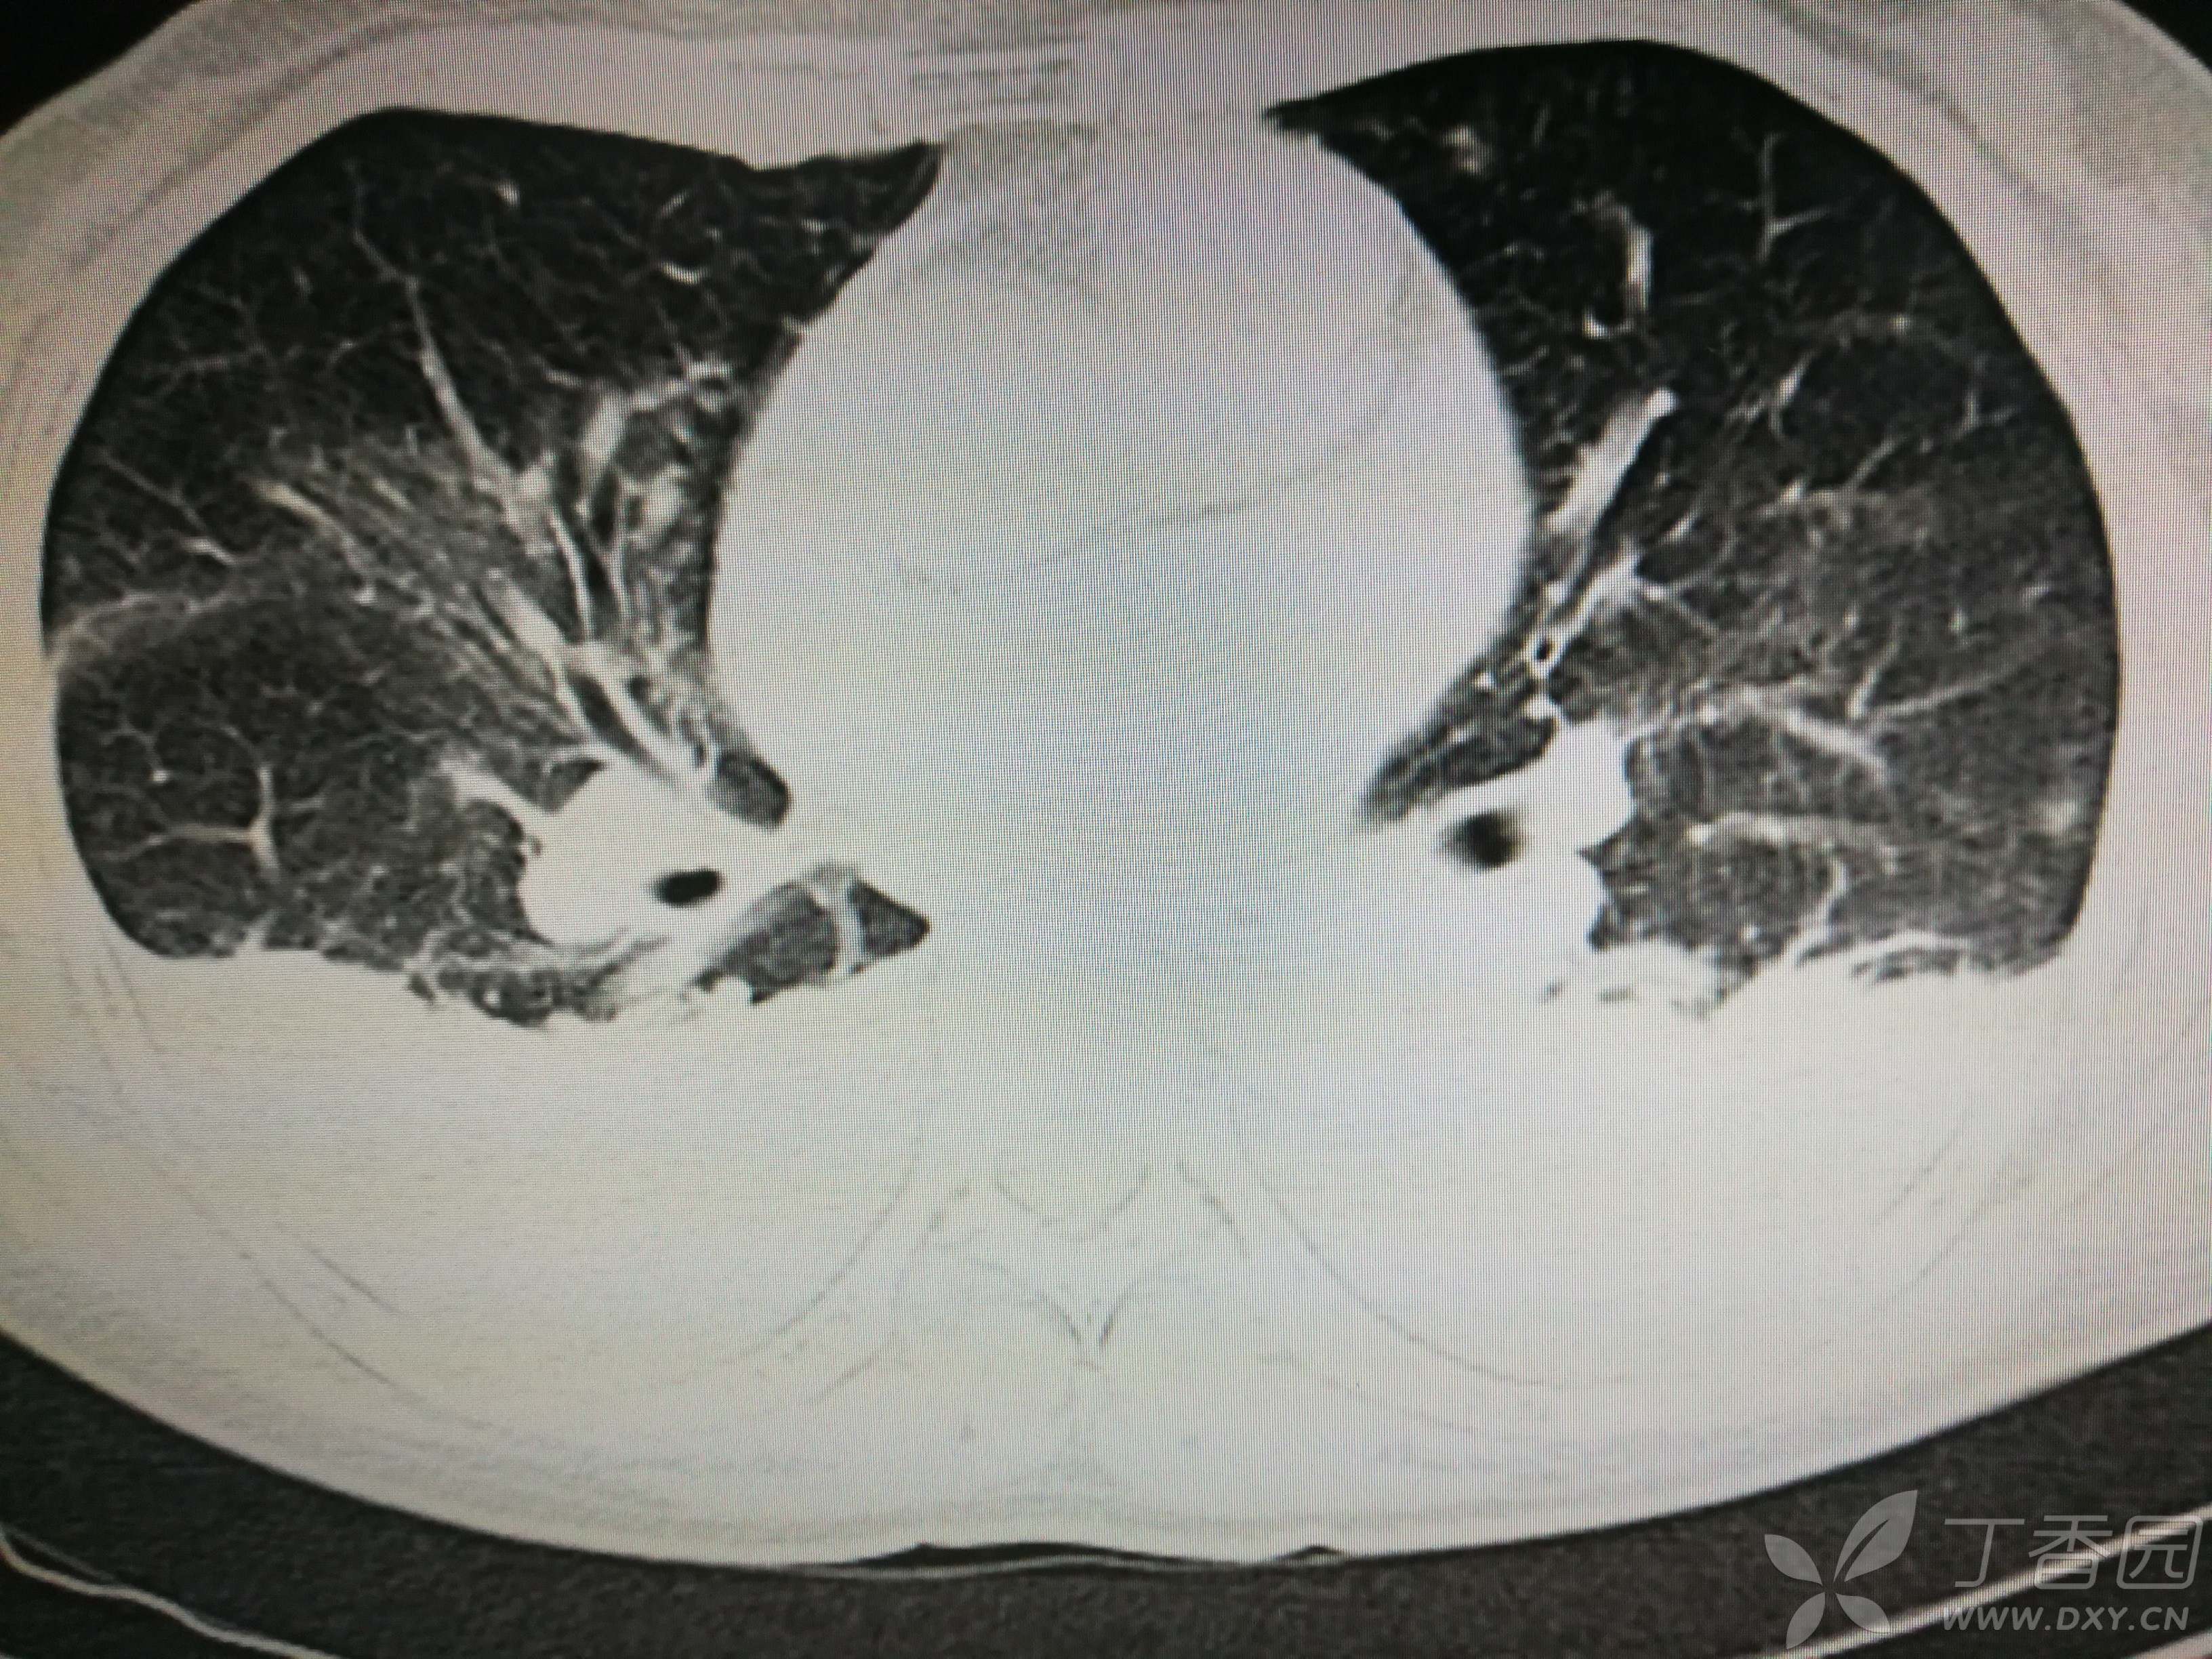

给予低分子肝素钙针抗凝、七叶皂苷钠针消肿及骨牵引固定等等治疗。入院后第四天行“左侧股骨下段骨折切开复位内固定术”(术前查双下肢彩超:双下肢深静脉血流通畅),手术顺利,术后予预防感染、预防血栓形成等治疗。术后患者无明显发热,生命体征平稳。术后第四天复查血常规:白细胞13.4×109/L,血红蛋白84g/L,血小板在正常范围。生化:白蛋白35.7g/L,余无明显异常。当天,患者开始出现轻度胸闷气急,可耐受。术后第五天患者胸闷气急加重,无胸痛,无背痛,无咯血,无意识障碍,无头晕头痛,无恶心呕吐等,急查凝血功能:纤维蛋白原降解产物12mg/L,D二聚体4000ug/L,余无明显异常。查动脉血气分析:pH7.52,氧分压62mmHg,二氧化碳分压30mmHg,碱剩余1.8mmol/L,乳酸1.0mm/L,血红蛋白86g/L。查胸部CT见下(先视频后图片):